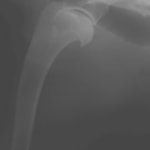

症例1:グレート・ピレニーズ、11歳齢、避妊メス

慢性的な右前肢跛行、右肩関節伸展時の顕著な疼痛身体検査において、棘上筋、棘下筋および上腕筋群の顕著な萎縮を認めた。

初回レントゲン:明らかな骨病変は認められない

CT検査

上腕骨近位内側領域を中心に不正な骨増生疑う所見